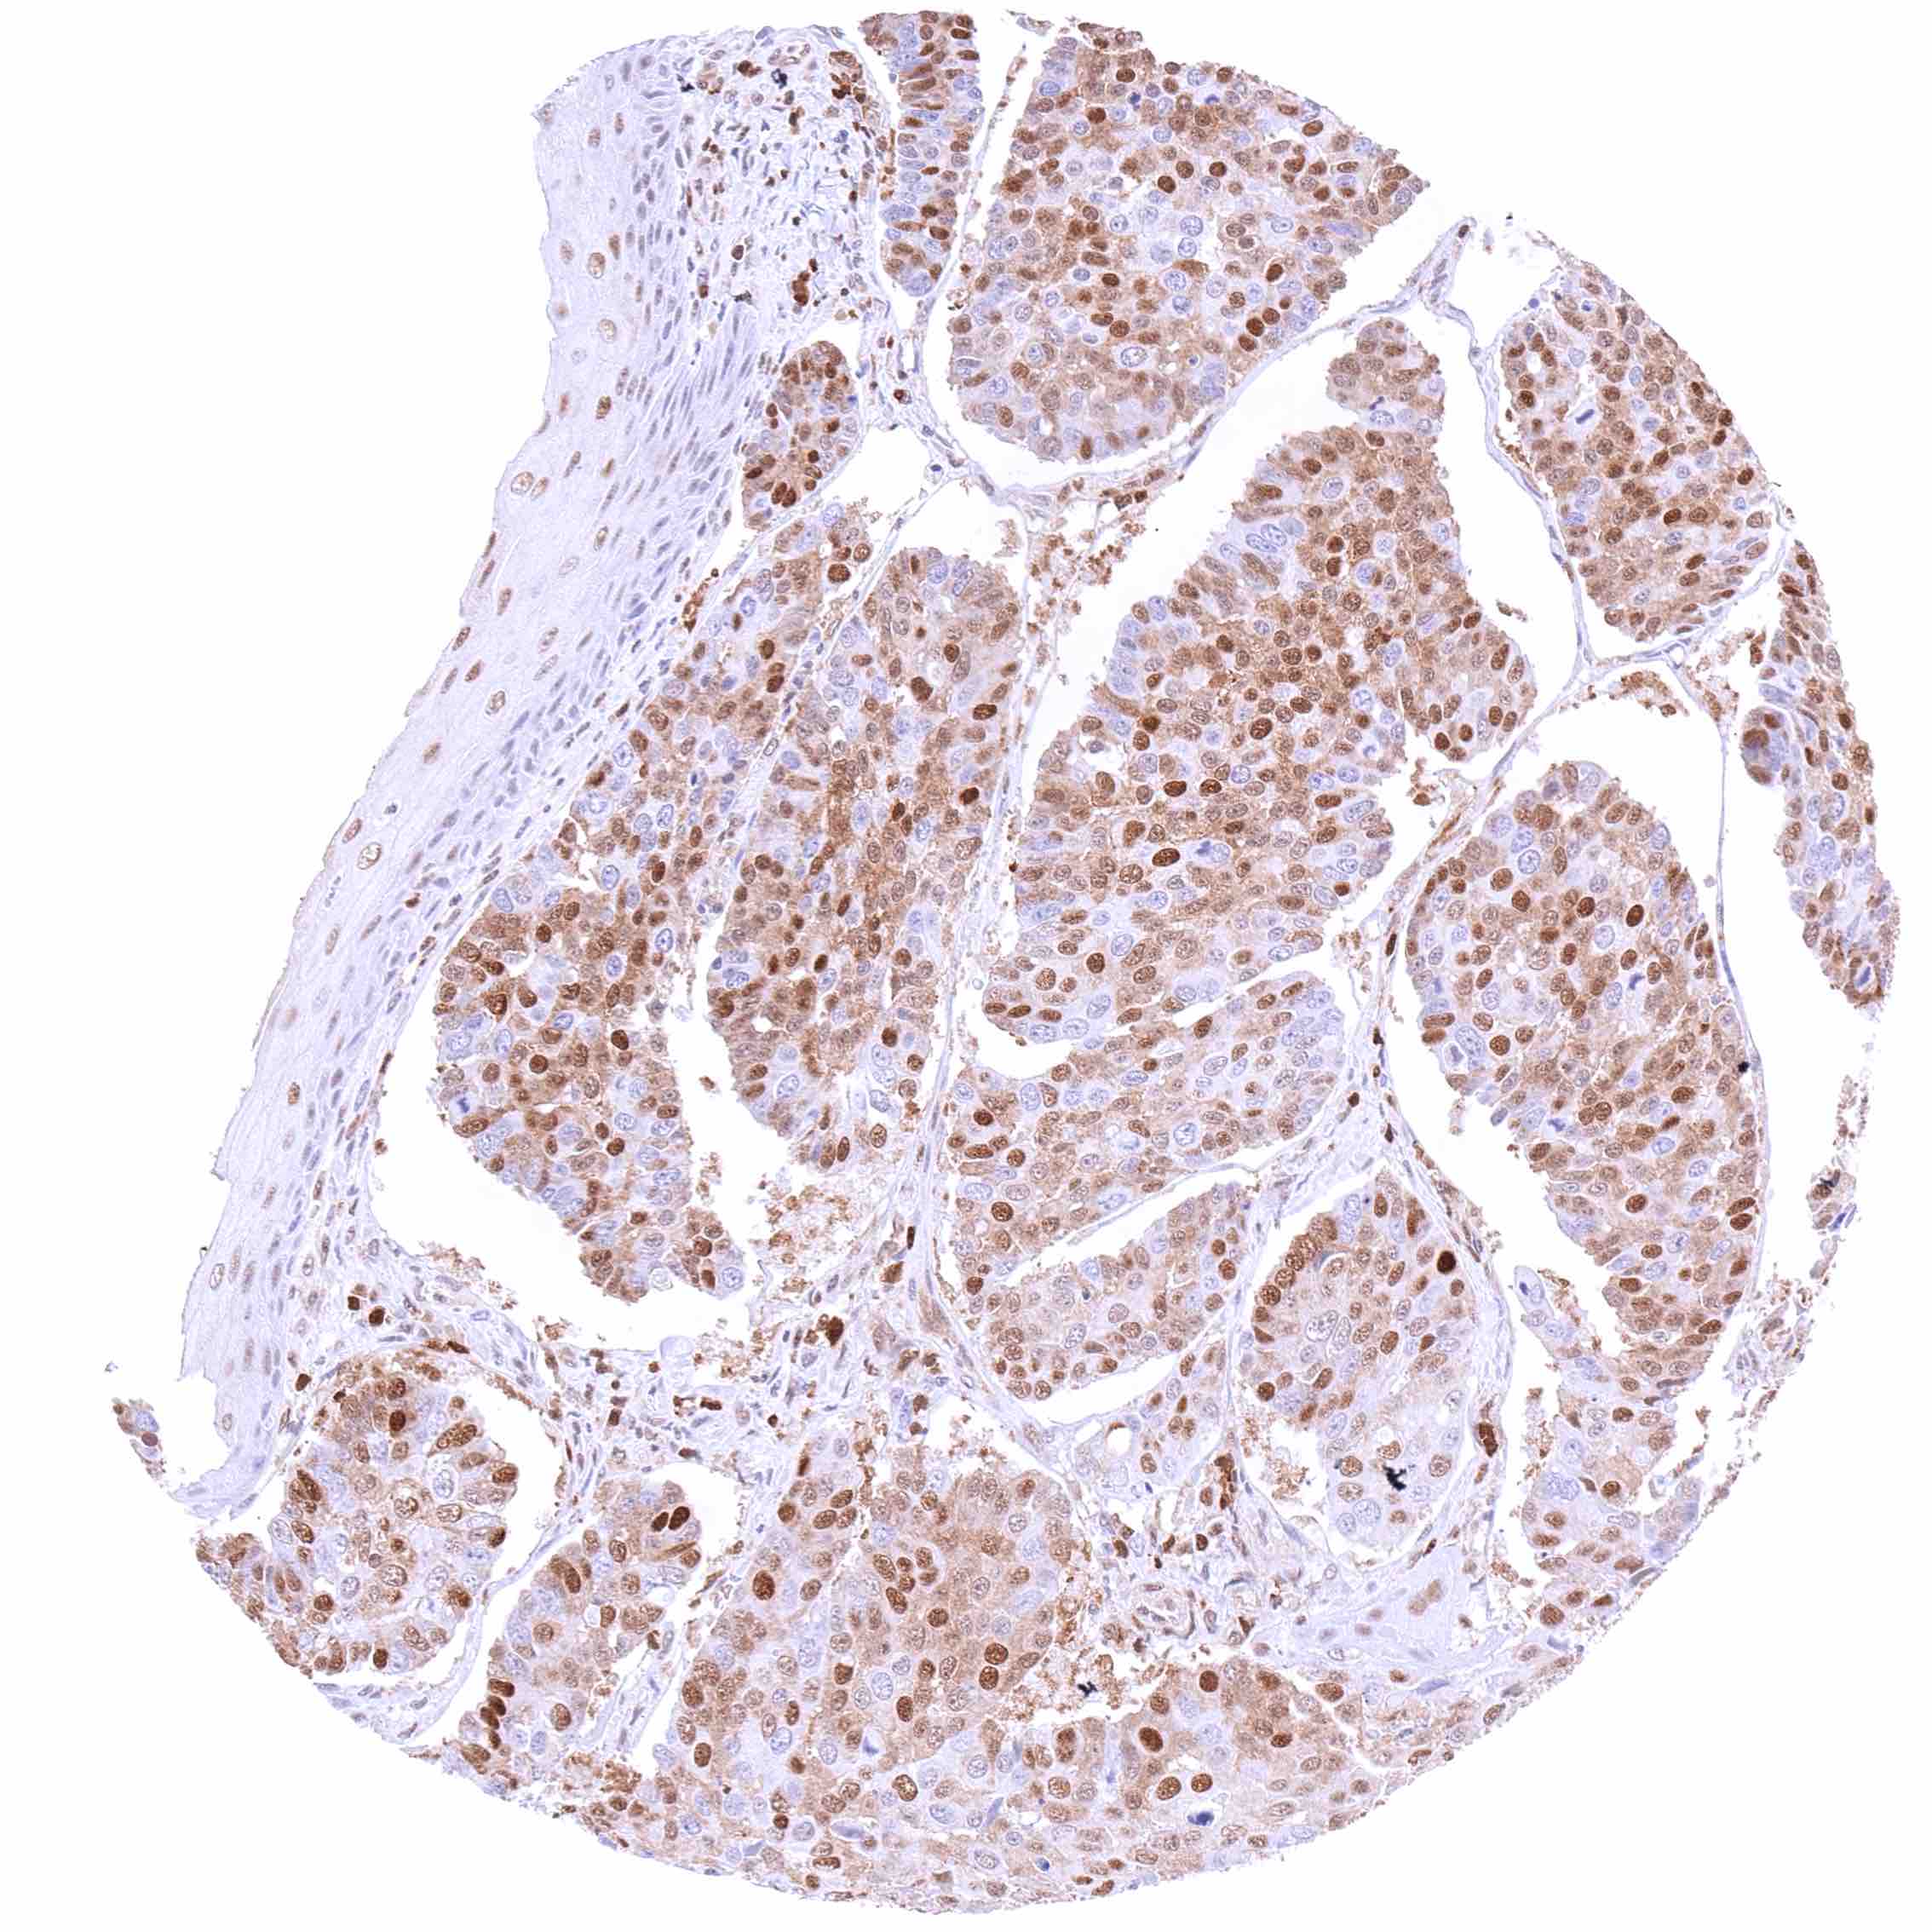

Pancreas – Neuroendocrine tumor with strong, predominantly nuclear p27 positivity of tumor cells.